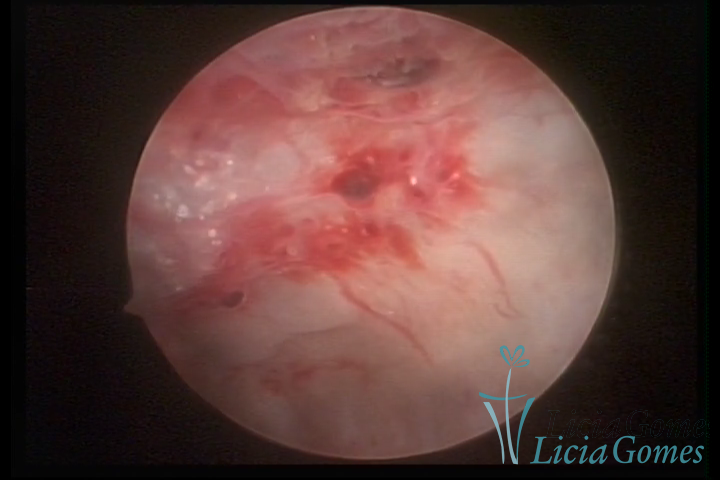

ADENOMIOSE

É a presença de tecido endometrial na camada muscular do útero

A vídeo-histeroscopia permite diagnosticar às lesões próximas às camadas miometriais superficiais, próximo ao endométrio visualizando lesões de coloração violácea, circunscritas, ou acastanhadas com conteúdo achocolatado.